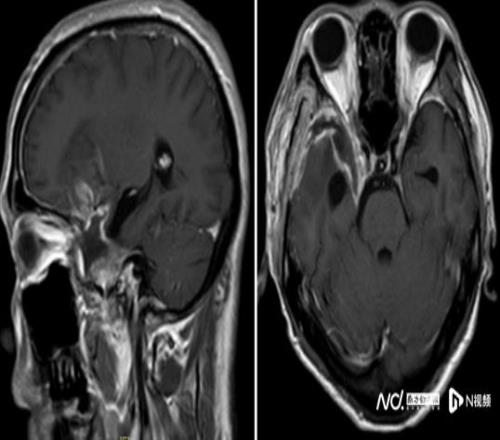

經(jīng)過近8個小時的精細(xì)操作,腫瘤被完整切除,重要神經(jīng)血管結(jié)構(gòu)完好保留。術(shù)后患者恢復(fù)良好,順利出院,經(jīng)過積極康復(fù)后,陳叔有望重回馬拉松賽場。